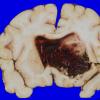

NEOPLASMS (HEMATOLYMPHOID)

Granulocytic Sarcoma (2)